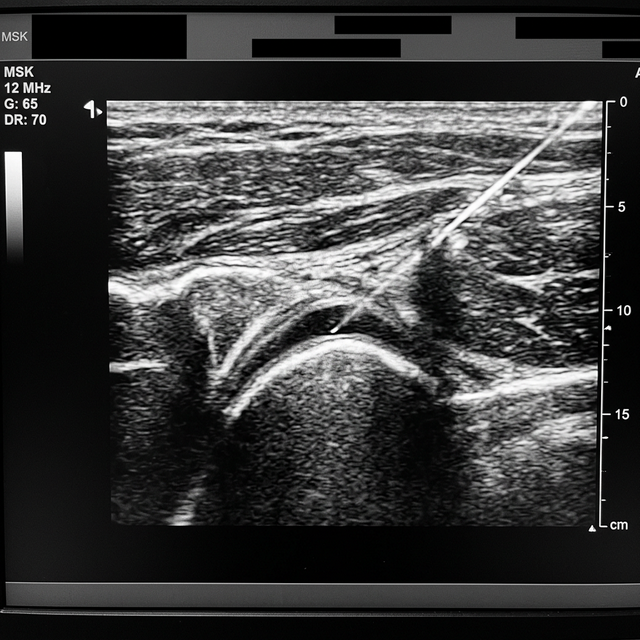

1. Millimetre Precision: The needle tip is visualised in real-time on the monitor. Dr Sankaye can navigate the needle past critical blood vessels and nerves directly into the inflamed bursa, joint space, or tendon sheath.